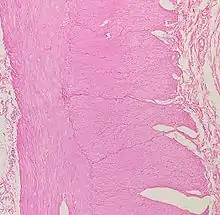

Histología del intestino grueso

Presenta criptas de Lieberkühn, no tiene vellosidades ni pliegues circulares.[44] Presenta, en la túnica serosa, evaginaciones. Una evaginación llena de tejido adiposo constituye un apéndice omental.

En el intestino grueso hay una gran cantidad de exocrinocitos caliciformes. Las poblaciones celulares epiteliales son las mismas del intestino delgado.[45][46]